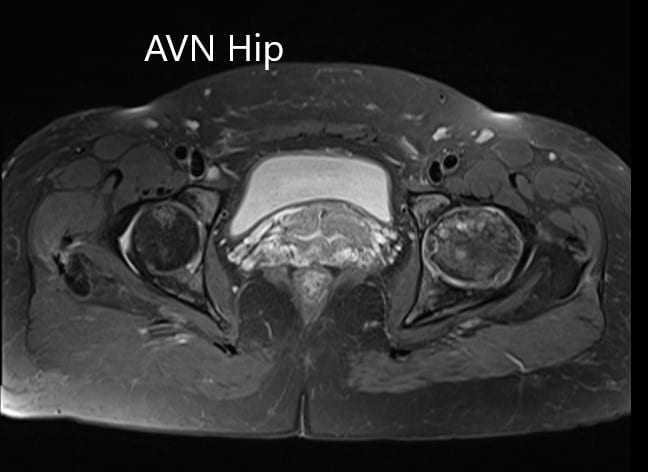

An MRI was obtained which showed altered signal intensity in both T1WI and T2WI. There was a subtle collapse of the left femoral head. A serpiginous hyperintense line was seen on T2WI demarcating an area of osteonecrosis in the left femoral head. This area involved the lateral and medial compartment and covered more than 50% of the surface area of the head.

Secondary osteoarthritic changes were visualized in the form of reduction of anterosuperior joint space and osteophyte formation. A small amount of fluid was seen in the joint cavity.

T1WI and T2WI of the MRI showing an axial section of the bilateral femoral head.